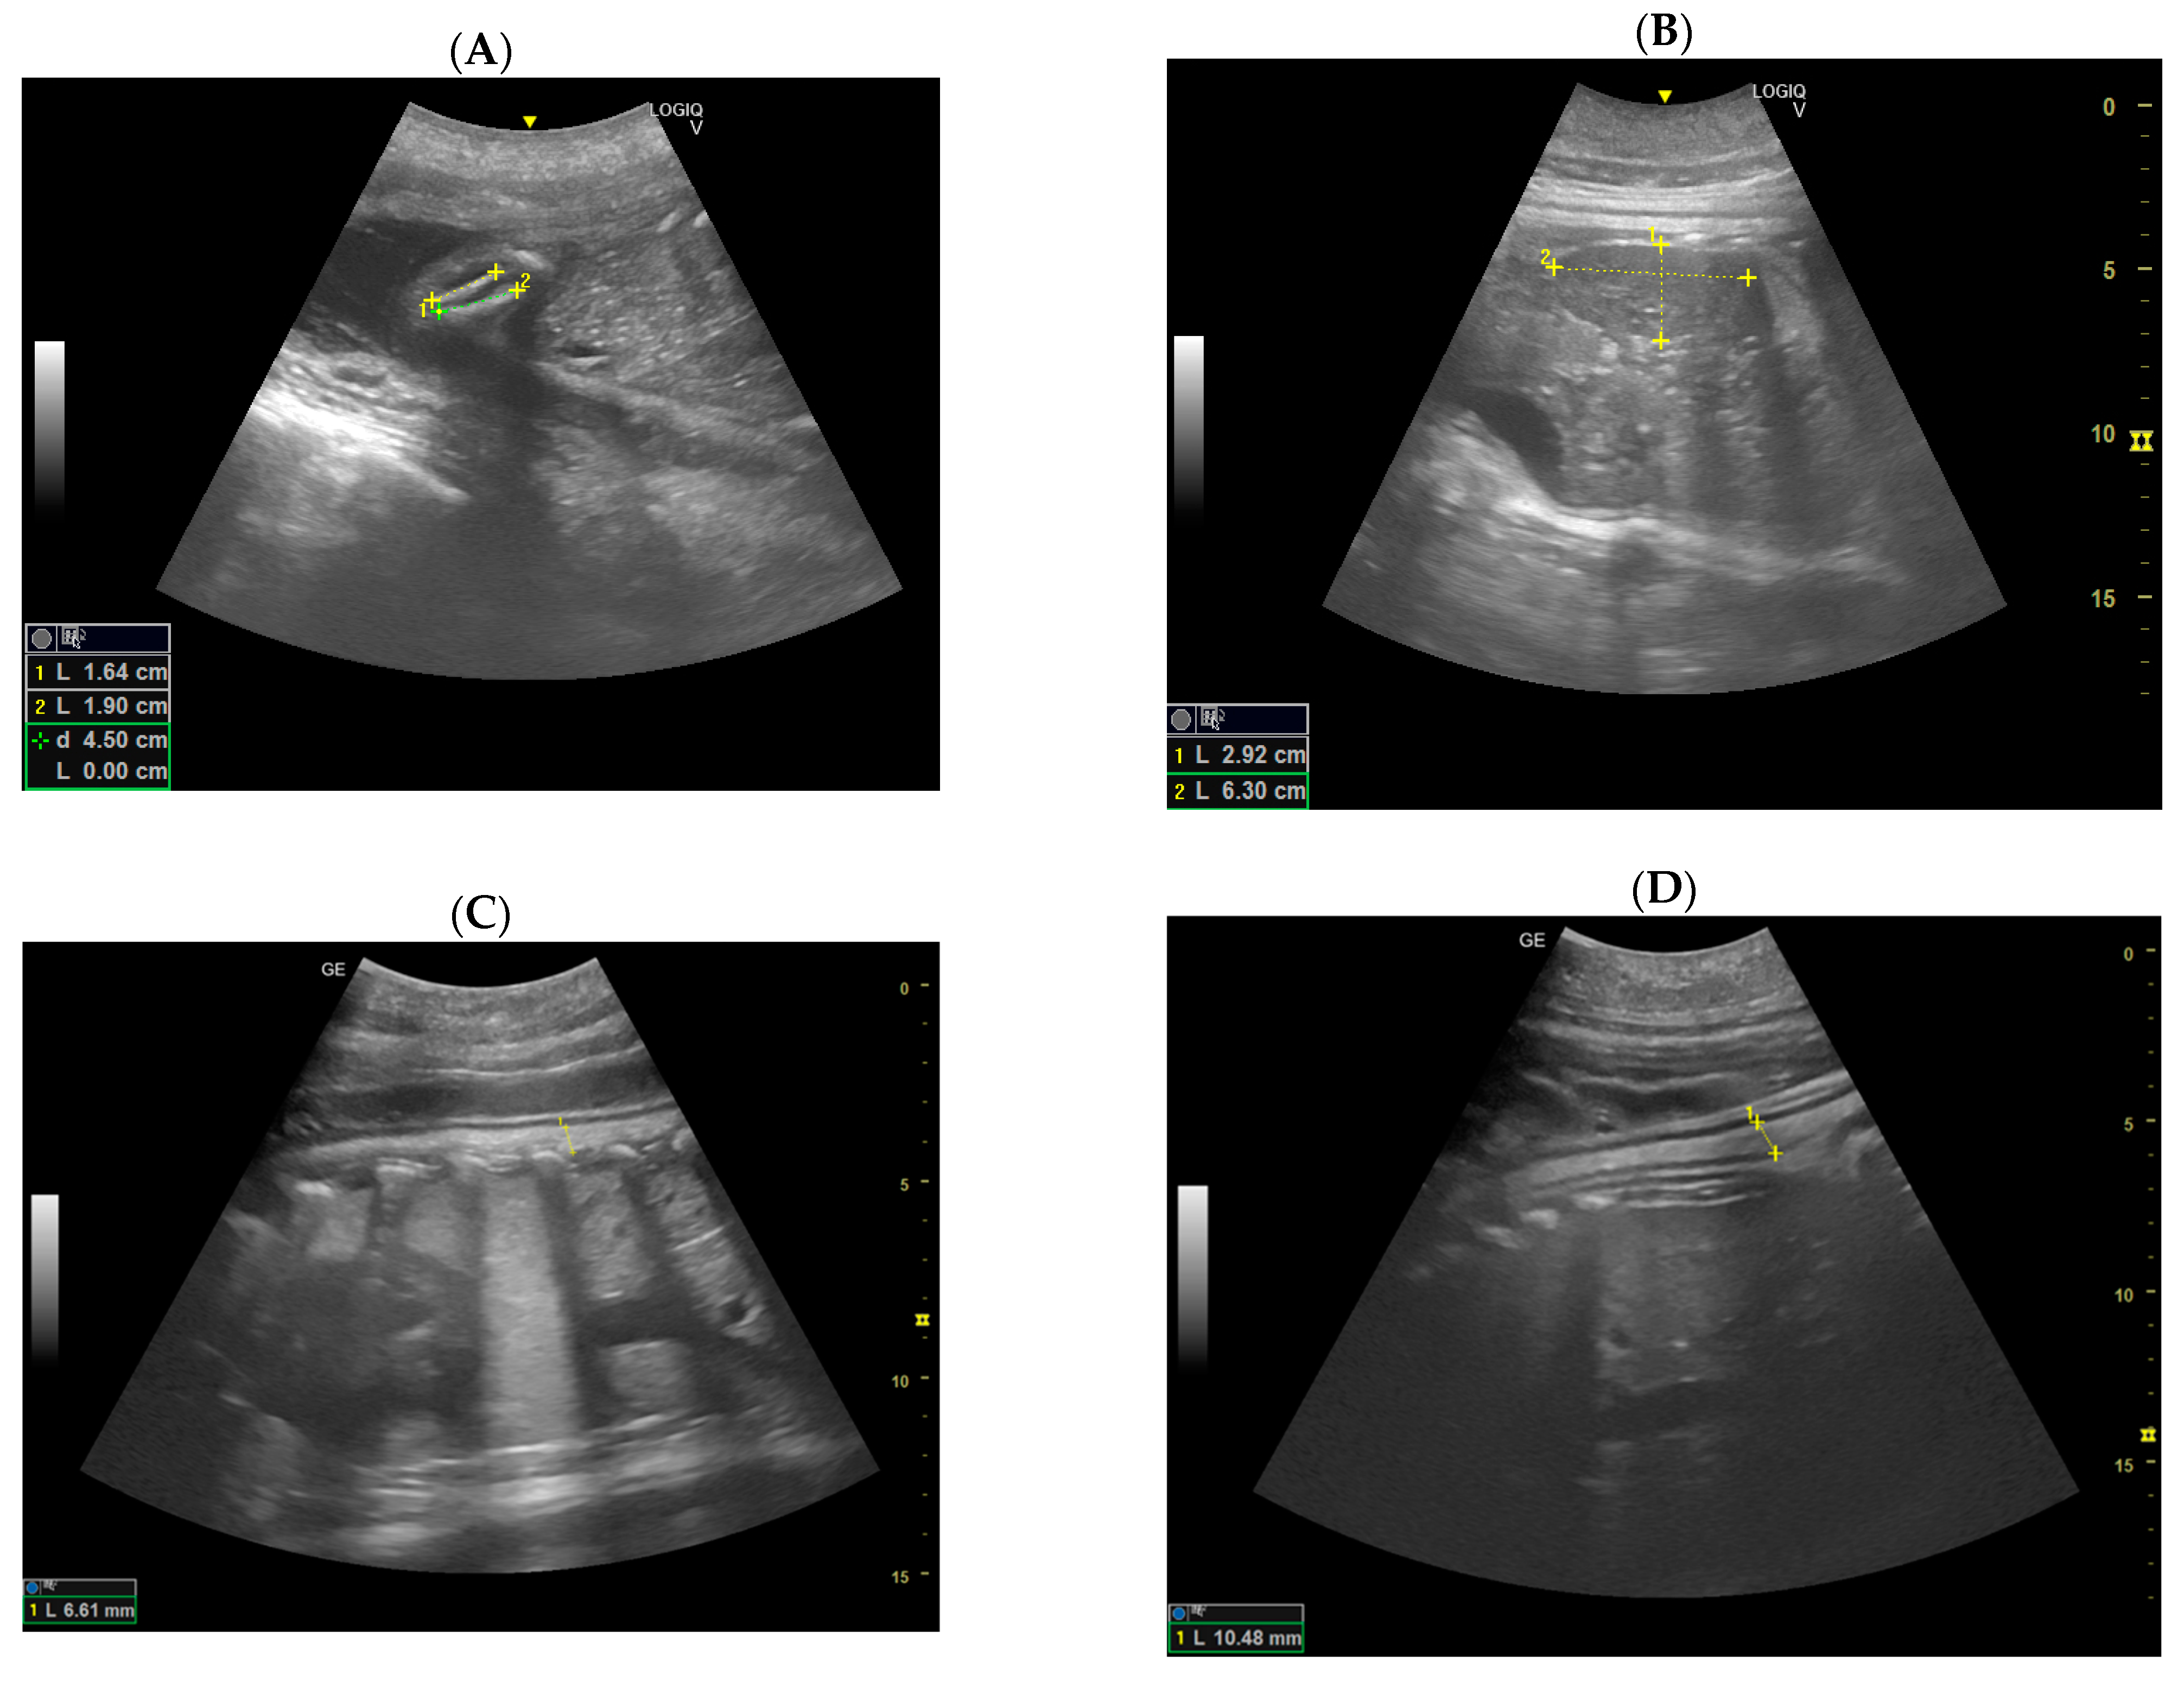

3.3. Construction of the Growth Curve of the Embryonic and Fetal Blubber Thickness

3.5. Construction of the Growth Curve of the Blubber Thickness